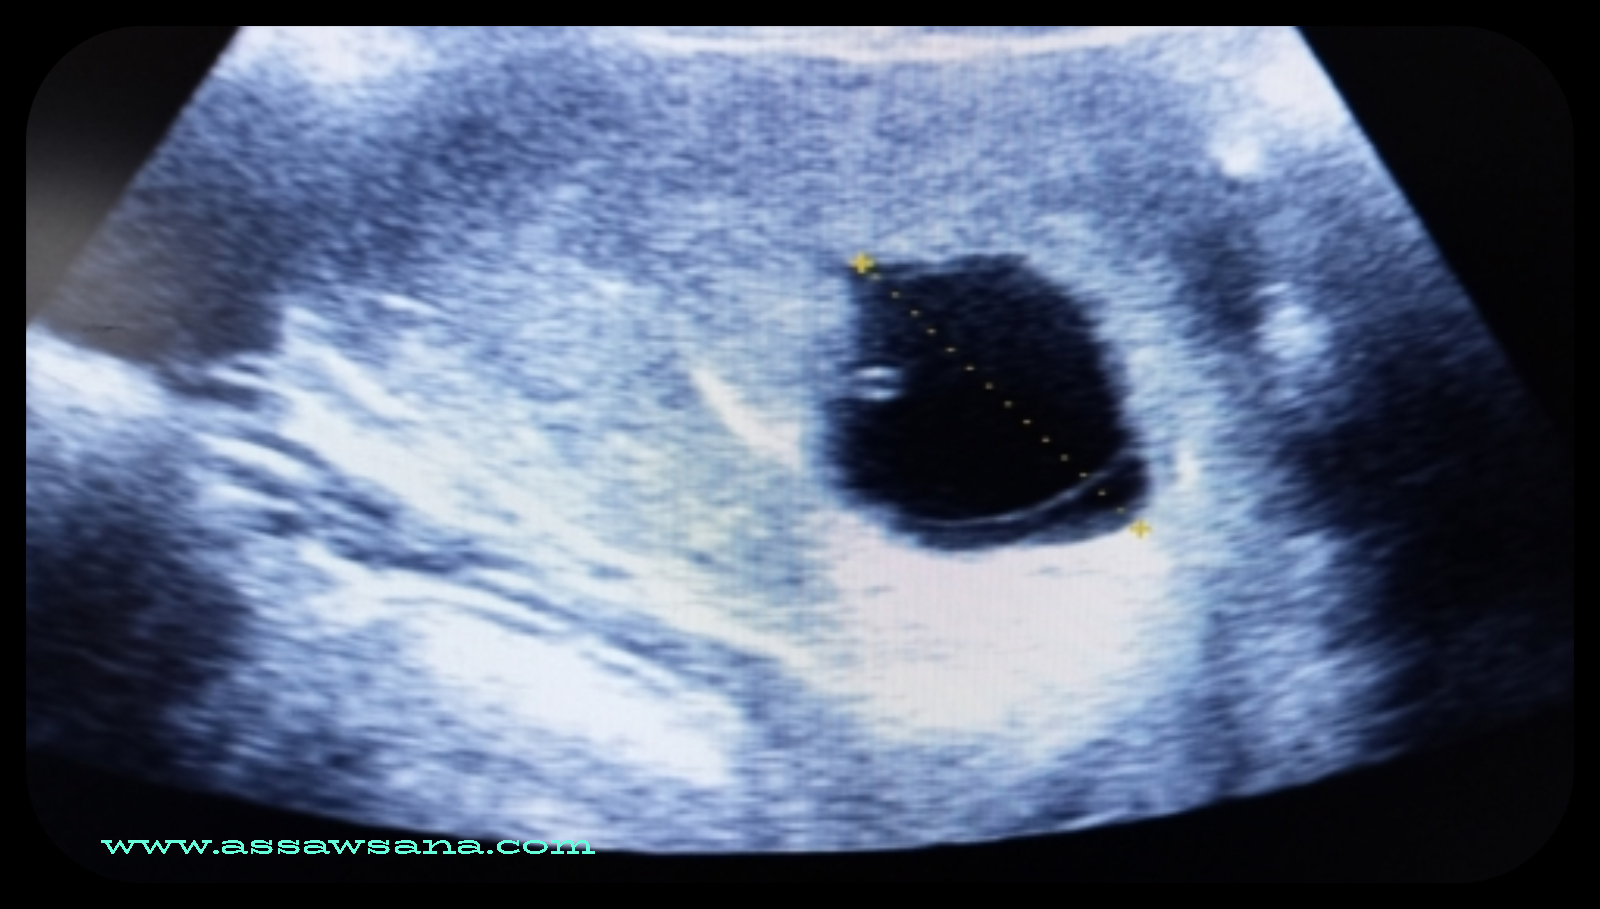

كيس الحمل الفارغ

السوسنة- كيس الحمل الفارغ هو حالة تحدث عندما يتشكل كيس الحمل في الرحم، ولكن لا توجد بدايات لتطور الجنين داخله. تُعتبر هذه الحالة نتيجة لفشل عملية الإخصاب أو الانقسام الجنيني، وغالبًا ما تُكتشف خلال الفحوصات الروتينية بالموجات فوق الصوتية. يُعد كيس الحمل الفارغ من الأسباب الشائعة للإجهاض المبكر، ويمكن أن يتسبب في مشاعر من الحزن والقلق لدى النساء اللواتي يمررن بتجربة الحمل. من المهم تقديم الدعم النفسي والطبي للنساء في هذه الحالة لضمان سلامتهن الصحية والعاطفية.

يتمثل الحمل غير المكتمل الذي يُعرَف أيضاً بالبويضة التالفة (بالإنجليزية: Blighted Ovum) بانغراس البويضة الملقحة في جدار الرحم ونمو كيس الحمل دون نمو الجنين، ممّا يؤدي إلى نمو كيس حمل فارغ، وقد تكون هذه الحالة ناجمة عن وجود بعض الاضطرابات الجينيّة في البويضة الملقحة، وقد لا يتمكّن الطبيب من تحديد المسبّب الرئيسيّ للمشكلة في العديد من الحالات، كما تجدر الإشارة إلى أنّ اكتشاف تشكّل كيس الحمل الفارغ يعني فشل الحمل، وبالتالي حدوث الإجهاض، وقد يتمّ الانتظار حتى حدوث الإجهاض بشكلٍ تلقائي من الجسم، وقد يُجرّض الطبيب الإجهاض، ومن الجدير بالذكر أنّ هذه الحالة يتمّ اكتشافها في الفترة بين الأسبوع 8-13 من الحمل في العادة، وقد تحدث قبل اكتشاف المرأة للحمل في بعض الحالات.